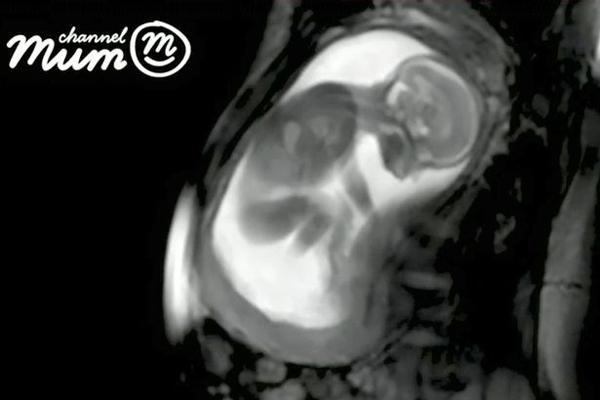

Trong đoạn video kéo dài 20 giây, hình ảnh thai nhi đang nghịch dây rốn, xoay đầu từ bên này sang bên kia, co duỗi người được thể hiện khá rõ nét. Ở những giây kết thúc, em bé thậm chí còn co người đạp mẹ một cái khá mạnh khiến bụng biến dạng.

Hình ảnh em bé đang nghịch dây rốn được chụp lại rõ ràng.